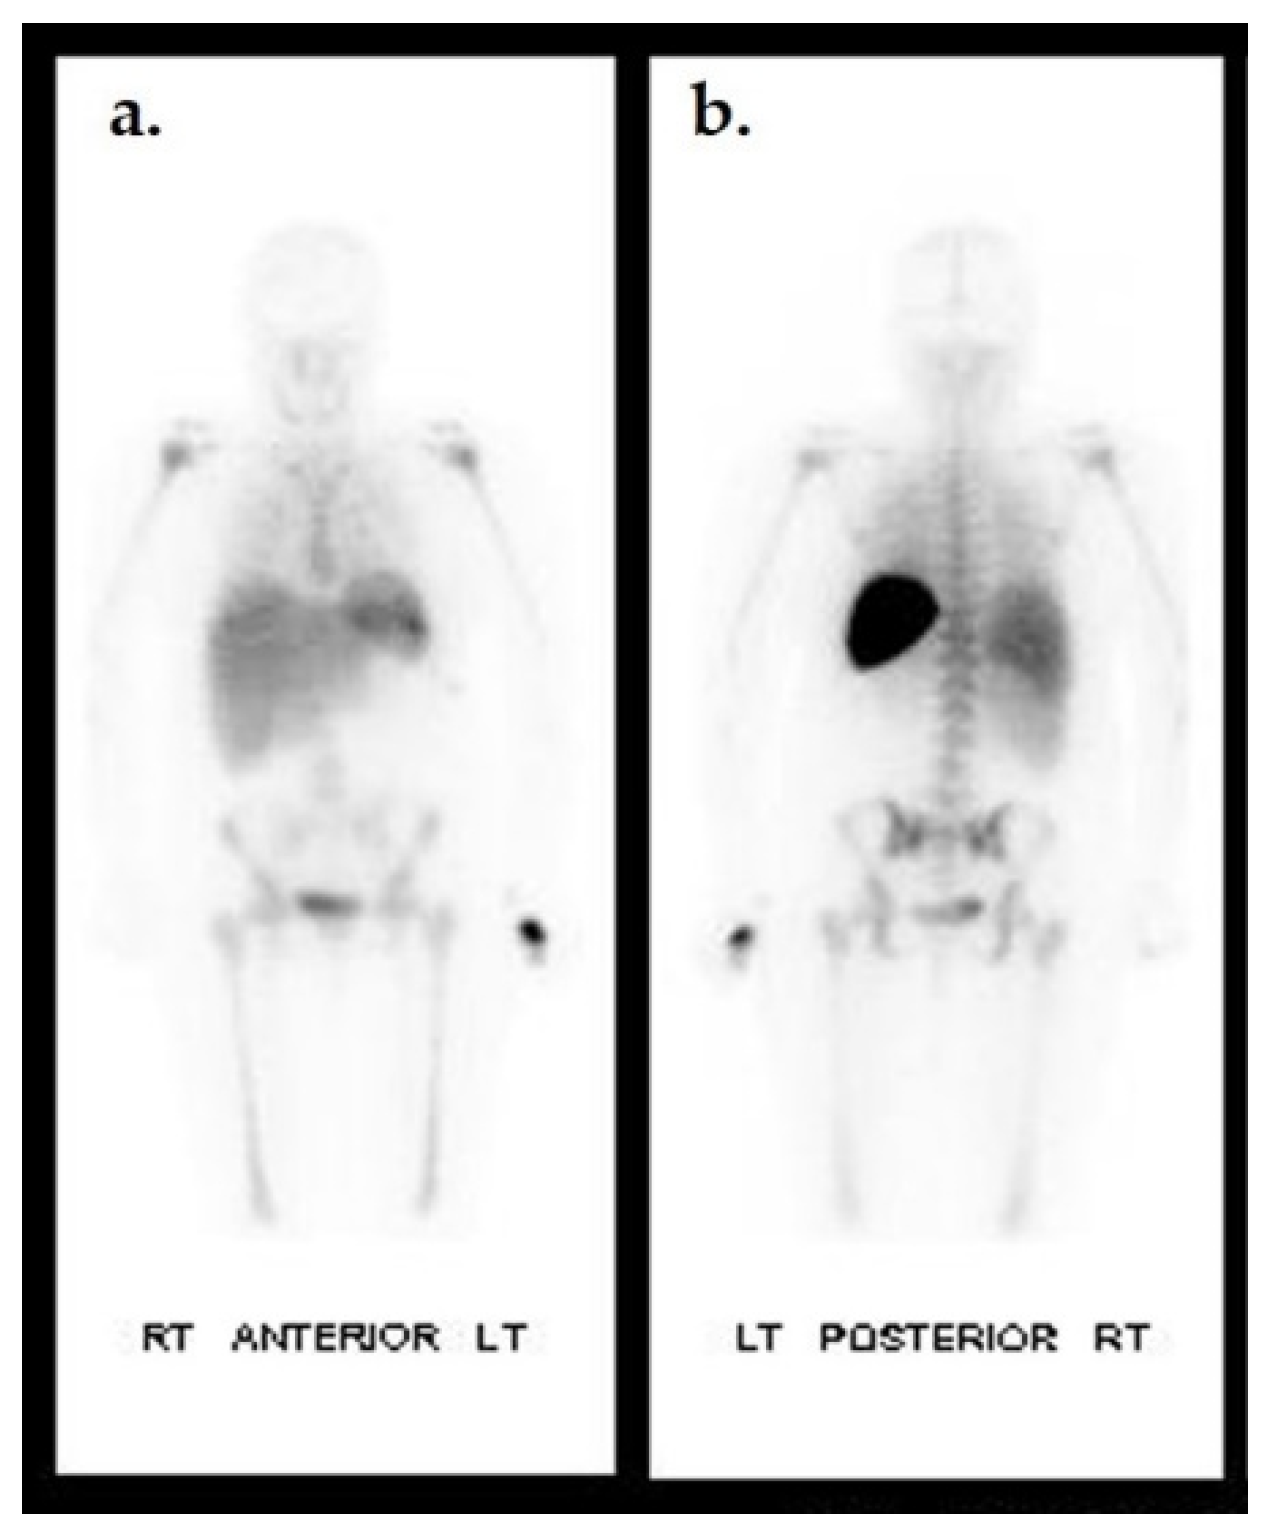

- Erdman, W.A.; Buethe, J.; Bhore, R.; Ghayee, H.K.; Thompson, C.; Maewal, P.; Anderson, J.; Klemow, S.; Oz, O.K. Indexing severity of diabetic foot infection with 99mTc-WBC SPECT/CT hybrid imaging. Diabetes Care 2012, 35, 1826–1831. [Google Scholar] [CrossRef]